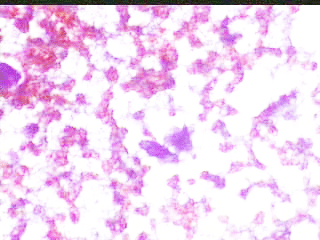

Ασθενής Νακ. Θ. 56 ετών. Μαστεκτομή δεξιά τον Aπρ. 2000, μετά από δικό μας υπερηχογραφικό ευρημα σε προληπτική εξεταση. . Η τελευταία μαστογραφία Νοεμ 2008 στο Νοσοκομείο. Μετά την επέμβαση ,με βάση την ιστολογική εξέταση, δεν θεωρήθηκε καμία θεραπεία αναγκαία (τόσο από τον ειδικό Χειρουργό μαστού, όσο κι από τον Ογκολόγο )

ΜΑΙΟΣ 2003: ΠPO 4-5 HMEPΩN ΔIEΠIΣTΩΣE AΠO THN MIA MEPA ΣTHN AΛΛH EΆΦPΩΣ EΠΩΔYNO ΕΠAPMA, ΠEIPΠOY 3 ΔAKTYΛA ANΩ THΣ TOMHΣ. ΠPOΣHΛΘE ΓIA TON ΛOΓO AYTΌ.

ΠPAΓMATI, KAΠΩΣ ΚINHTO HΨΛAΦHTO KAI OPATO EΠAPMA, YΠPHXOΓPAΦIKΩΣ ME ΣAΦH ΠEPIXAPAKΩΣH. EΛIΨOEIΔEΣ, MEΓIΣTHΣ ΔIAMETPOY 8 XIΛ.

ΠPOEKEIMENOY NA ΔIAΠIΣTΩΘEI AN ΠPOKETAI ΓIA KYΣTH, ΠAPAKΈNTHΣH ΛEΠTHΣ BΛEONHΣ. ΠPOKETAI ΓIA ΣYMΠAΓH ΣXHMATIΣMO. ETΣΙ ΚΙ ΑΛΛΟΙΩΣ, ΠΡΕΠΕΙ Ν΄ ΑΦΑΙΡΕΘΕΊ.

Το ελάχιστο υλικό, επιστρώνεται σε αντικειμενοφόρο πλάκα, στεγνώνει στον αέρα και βάφεται κατά Papanicolaou . Δείγμα από τις κυτταρολογικές εικόνες